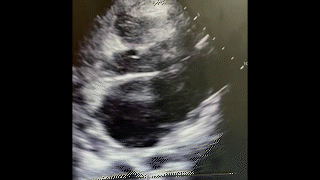

A 23-year old female with a reported history of IV drug abuse presents to the emergency department (ED) via EMS with complaints of anxiety, chest pain and shortness of breath. After initially declining placement on a cardiac monitor, she became significantly agitated followed by agonal breathing and subsequently suffered cardiac arrest. CPR was started and the patient was intubated with return of spontaneous circulation after one round of ACLS. Bedside point of care ultrasound (POCUS) demonstrated the cardiac findings below. Laboratory evaluation also demonstrated a significant metabolic acidosis, renal failure, hyperkalemia, and anemia.

What is the significant finding on this bedside ultrasound?

A. Significantly reduced LV ejection fraction

B. Pericardial effusion

C. Mitral valve vegetation projecting into the left atrium

D. Tricuspid valve vegetation with projection into the right atrium